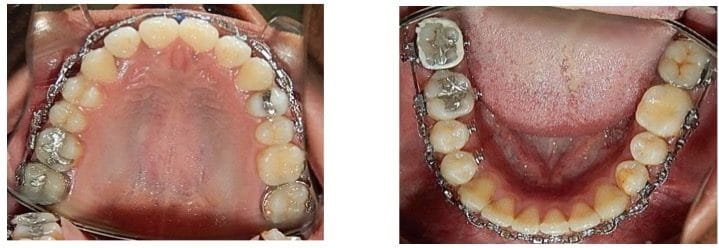

En la vista oclusal superior e inferior, se muestra la forma oval las arcadas. (Fig. 8 A y B)

Fig. 8. Fotografías oclusales. A) Superior. B) Inferior.